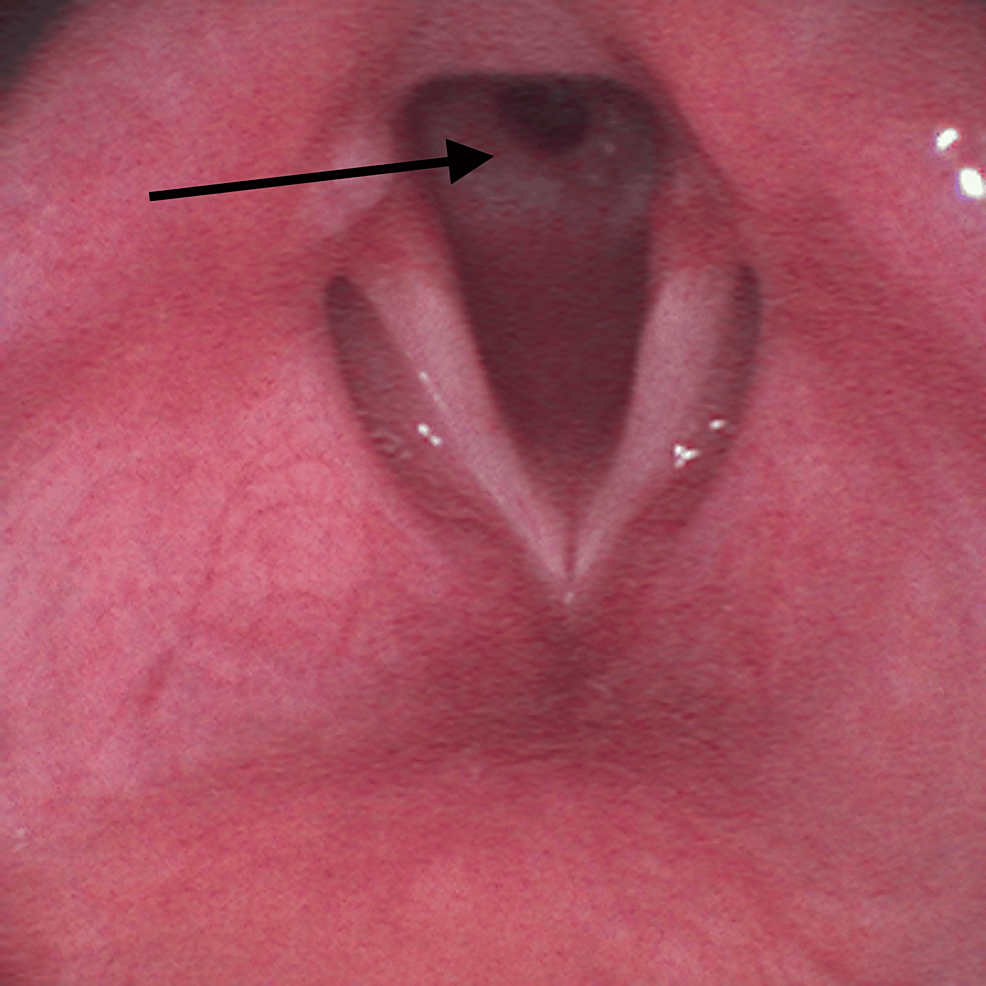

On the surgery day, a reassessment of his airway management plan was performed by a multidisciplinary team including anesthesiologists and otorhinolaryngologists. It was decided to make an asleep fiberoptic visualization of the lesion through a supraglottic device. After adequate pre-oxygenation, endovenous induction was performed using a target-controlled infusion (TCI) of propofol, Schneider model with target effect-site concentration of 4 µg/mL, and of remifentanil, Minto model. A dose of 60 mg of rocuronium was administered and a supraglottic device, AuraGain® size number four was introduced without trauma. Total intravenous anesthesia was maintained using the referred TCI. While maintaining volume-controlled ventilation with a maximum inspiratory pressure of 20 cmH2O, an Ambu® aScope™ 4 Broncho Slim 3.8/1.2 (Ambu A/S, Ballerup, Denmark) was introduced through the laryngeal mask and a circumferential fibrous membrane just below vocal cords was observed (Figure 2).